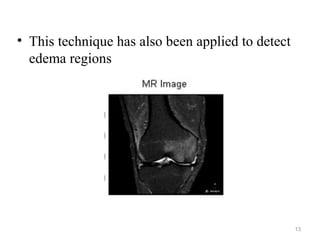

• This technique has also been applied to detect

edema regions